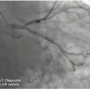

Right coronary artery (RCA): The RCA is 100% occluded. It is diffusely diseased in its proximal and mid portion with mid 100% occlusion. There is evidence of left to right collaterals.

Giving the patient’s angiographic findings, we elected to intervene on the RCA. We upsized the sheath to a 6 Fr Glidesheath in the right radial artery and used an Amplatz left (AL) 1 guide catheter to engage the RCA. We accessed the left radial with a 5 Fr for a contralateral injection and used a 5 Fr JL4 guide catheter from the left radial. Bivalirudin (Angiomax, The Medicines Company) was administered, and using a 1.25 mm over-the-wire balloon and an Asahi Fielder wire (Abbott Vascular), we attempted to navigate the RCA. The wire kept deflecting into a side branch, although there seemed to be, at least on initial angiography, a “beak.” The wire continued to deflect into a side branch. Additional wires were then used, including a Pilot 150 wire (Abbott Vascular) and a Miracle Bros 3 wire (Abbott Vascular), both of which were unsuccessful. At this time, we elected to attempt a retrograde approach via a transcollateral. Left to right collaterals from the circumflex appeared to offer the most direct path. We wired into the LCX artery, but there was poor visualization trying to inject around the 5 Fr sheath. Therefore, we pulled everything, and upsized to a 6 Fr JL4 guide catheter.

Using a Fielder wire and a 1.25mm balloon, we attempted to cross through the septal. However, we could not find an adequate collateral via selective injection of the septal. We then went back to the circumflex artery using a Pilot wire and a 1.25mm Sprinter balloon (Medtronic). Initial attempts were unsuccessful; however, after selective injection through the balloon, an ideal channel was located and successfully navigated. In an attempt to advance the balloon, the guide and guidewire popped out, secondary to poor guide support. We were able to recross into the distal posterior descending artery (PDA). This was confirmed by selective angiogram after advancing the 1.25mm balloon through the collateral into the distal RCA. We exchanged for a Miracle Bros wire and tried to navigate the RCA in retrograde fashion. This was unsuccessful. We then took a Pilot wire, and with the Pilot 200, we were able to navigate the RCA in retrograde fashion. We snared the wire and externalized it in the right radial artery. This did result in fracture of the distal wire tip while trying to externalize it. However, the fracture took place in the right radial sheath and was easily managed.

At this point, over the soft end of the wire, we were able to advance a 1.5 x 15 mm balloon and predilate the proximal RCA. Despite predilation, we were unable to advance a retrograde wire (Terumo Runthrough) but could not advance it in a retrograde manner. We then tried to rewire with a Runthrough wire in antegrade fashion, but were unsuccessful. Repeat predilation was performed with unsuccessful antegrade wiring. The Amplatz guide was changed out for a 6 Fr JR4 with side holes, as we thought that perhaps the Amplatz was deeply engaged in a dissection, preventing luminal passage. At this point, we still had the soft end of the wire externalized from the right radial and the back end of the wire externalized through the left radial artery. We took a 1.5 x 20mm Rx balloon (Boston Scientific) and went from the left radial via the collateral in a retrograde fashion to predilate the vessel again. The vessel was predilated from distal to proximal. After proximal dilation, the patient dropped his pressure. There was concern about a possible perforation at this point. Injection of the left demonstrated good flow; however, there was not good flow in the right. The RCA system showed a dissection in what was the proximal portion of the right, but no staining.